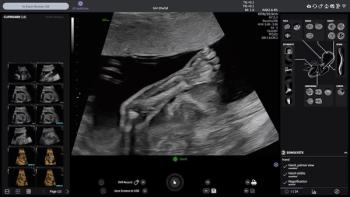

The Voluson Performance 18 and 16 ultrasound devices reportedly combine enhanced imaging capabilities with AI-enabled efficiencies.